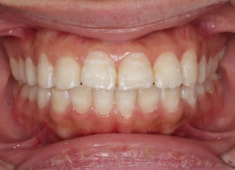

治療後(1年12ヶ月後)